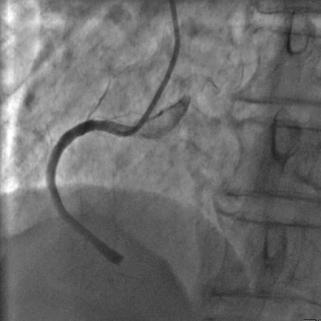

手術臺上,醫(yī)療團隊配合默契。冠狀動脈造影顯示右冠狀動脈遠段完全閉塞。董照輝主任快速操作,送入導引導管,PTCA導絲穿過閉塞血管送到遠端。球囊擴張后患者血壓突然下降,監(jiān)護儀警報響起。

冠狀動脈造影示:右冠狀動脈遠段閉塞